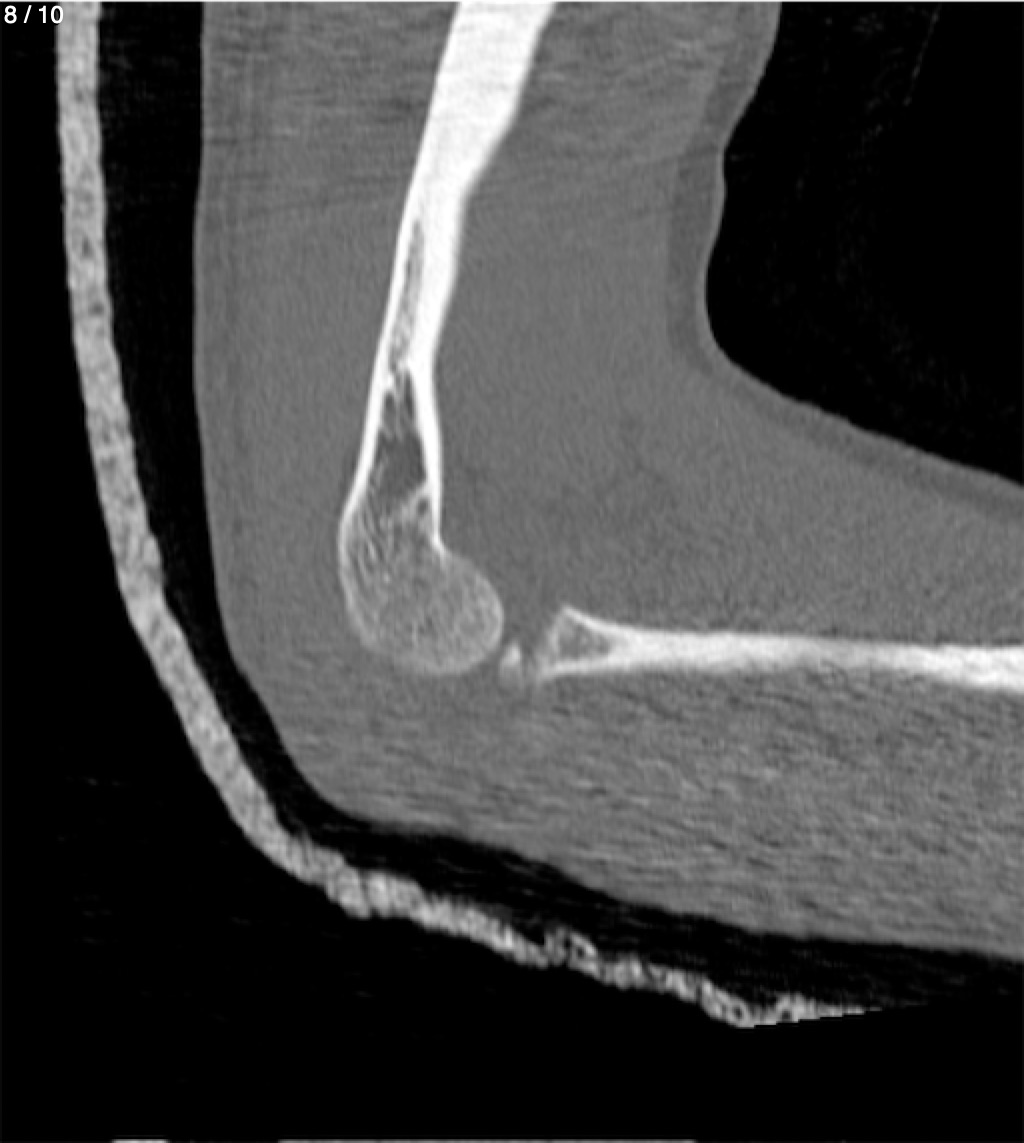

Antonio Dominguez Tino 21 A - Tac Codo Izq